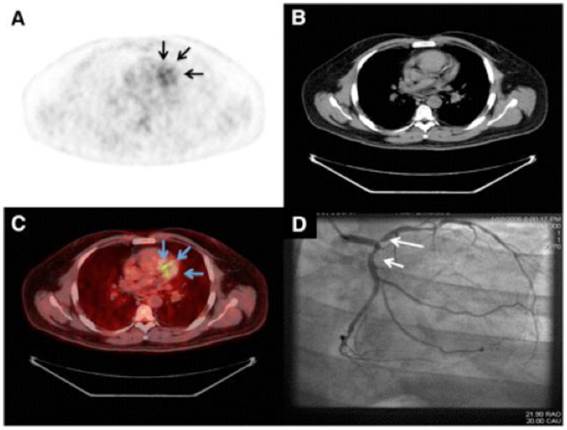

Fig 4

Imaging of the vulnerable plaques in human coronary atherosclerosis. Representative images of 18F-FDG PET (A), CT (B), PET/CT (C), and coronary angiography (D) from patient with good suppression with coronary 18F-FDG uptake (arrows). Reprinted with the permission of the Society of Nuclear Medicine from Wykrzykowska et al. [183]